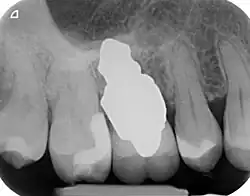

RAIs are custom made to perfectly fit the tooth socket of a specific patient immediately after tooth extraction. Therefore every implant is unique. As an optimised root-form it is much more than a simple 1:1 replica of a tooth. Since it exactly fills the gap left after the tooth is extracted, surgery is rarely needed. The implant can be produced from a copy of the extracted tooth, an impression of the tooth socket, or from a CT scan or CBCT scan.[7] The advantage of a CBCT scan is that the implant can be produced before extraction. With the former methods, it takes one or two days to fabricate an implant.

A root analogue implant can be fabricated from zirconium dioxide (zirconia) or titanium.[8] Successful titanium RAIs have been three-dimensionally printed as porous one-piece implants, using CAD software.[9] However, zirconia is the preferred material, because it is more esthetic in colour, with no grey discolouration visible through gums.[10][5]

- Natural form: a custom milled anatomic implant replicates the natural form of a tooth, so it simply fits into the tooth socket. Like the original tooth, a root analogue implant can have single- and multi-rooted forms.

A new attempt was made by Pirker et al 2004 in a human trial with root analogue zirconia implants, but this time by applying differentiated osseoingration on the surface. In 2011 he reported 90% success rate with this method in a 2.5 year human trial.[16]